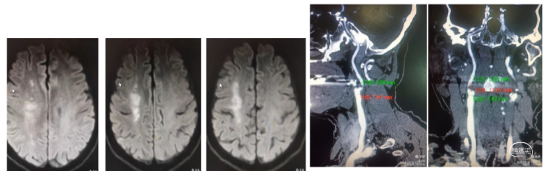

典型病例1: 患者,mshq 男性,44岁,“突发右侧上下肢无力,言语含糊”,溶栓后肢体肌力4-级,搀扶行走。经基层医院静脉溶栓后转入我院。外院核磁显示:左侧侧脑室后角梗塞。MRA显示:C4-C5段以远血管显影浅淡。

转入我科后,患者肢体较溶栓后略有加重,右下肢肌力3级,上肢2级。造影显示:左侧颈内动脉C1段呈火苗样窜动,提示:远端闭塞可能。说明病情在持续加重,可能为血栓堆积闭塞了血管。

入院后急查CT未见出血和低密度改变。核磁DWI示:左侧大脑半球梗塞,左侧大脑中动脉和内囊区域受累。MRA示:左侧颈内动脉未显影,考虑闭塞。

造影示:左侧颈内动脉起始部以远未向远端供血,左侧颈总动脉呈火苗样窜动。查询颈内动脉造影颈内动脉血流火苗样迟滞窜动。

核磁显示:左侧内囊区域梗塞,MRA示左侧颈内动脉未显影。考虑颈内动脉起始部狭窄急性血栓闭塞。行替萘普酶静脉溶栓后行血管内介入治疗。

核磁显示:右侧大脑中动脉上干区域梗塞,MRA示:右侧颈内动脉未显影,考虑闭塞。

病例简介:患者,LZhg,男,59岁,因"突发左侧上下肢无力6小时"入院。NiHSS评分10分。既往无糖尿病、高血压、房颤病史。CT无病灶,MRI示右侧大脑半球多发片状梗塞。MRA右侧颈内动脉系统未显影,考虑急性闭塞。